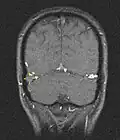

Sinus-/Venenthrombose, die nach einer SARS-CoV-2-Impfung aufgetreten ist. Abbildung (a) zeigt Blut im Subarachnoidalraum. Die Magnetresonanzangiographie (b) zeigt einen thrombotischen Verschluss des Sinus sagittalis superior (roter Pfeil) und des linken Sinus transversus (weißer Pfeil). Eine Nachuntersuchung zehn Tage später (c) unter Volldosis-Heparinisierung, unterstützt durch eine endovaskuläre Thrombektomie der Sinus, bestätigte die Wiederöffnung des Sinus sagittalis superior (gelber Pfeil) und des linken Sinus transversus (grüner Pfeil).